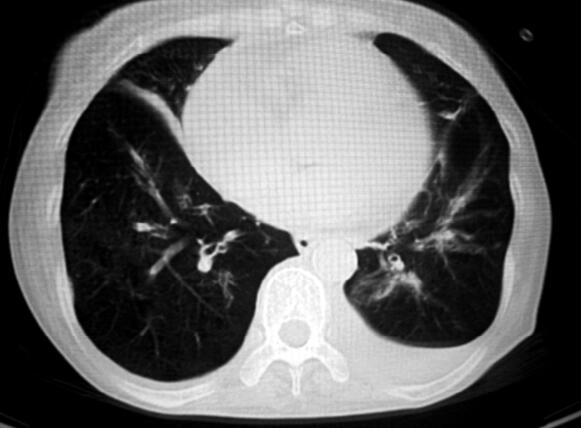

4.胸部CT:肺气肿,双肺多发肺大泡(图1)。

图1

患者此次病情加重后有发热,咳黄色黏痰,结合血常规和痰涂片的结果提示存在细菌感染,多数慢阻肺急性加重由细菌感染诱发。血气分析提示患者存在重度的二氧化碳潴留,严重的呼吸性酸中毒,Ⅱ型呼吸衰竭,同时证实了患者的神志障碍应该与二氧化碳的升高有关。血电解质结果提示患者存在低钾、低氯,这在慢阻肺急性加重患者中是比较常见的。胸部CT排除了支气管扩张、弥漫性泛细支气管炎及肺结核等引起慢性咳嗽的其他疾病,并提示有肺气肿和多发肺大泡。